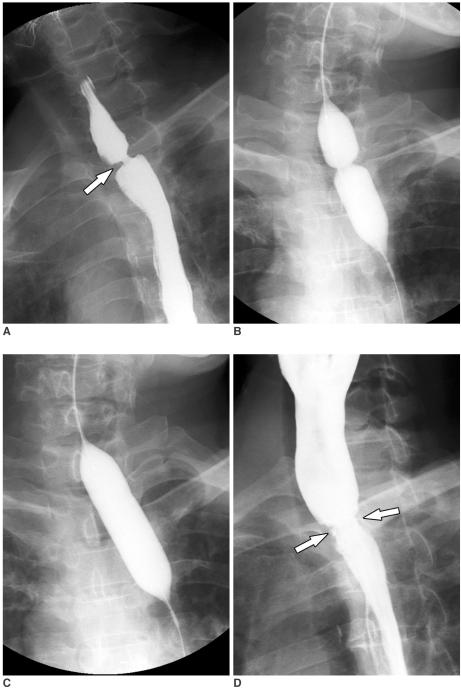

Fluoroscopically guided balloon dilation for benign anastomotic stricture in the upper gastrointestinal tract.

A benign anastomotic stricture is a common complication of upper gastrointestinal (UGI) surgery and is difficult to manage conservatively. Fluoroscopically guided balloon dilation has a number of advantages and is a safe and effective procedure for the treatment of various benign anastomotic strictures in the UGI tract.